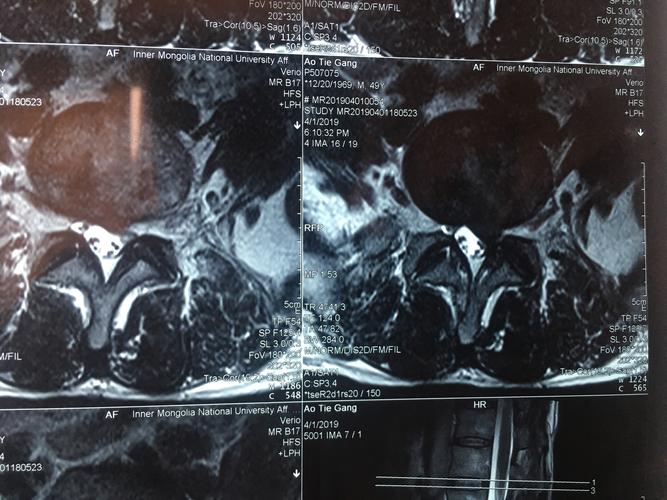

腰5骶1 核磁横断面 纤维环破裂 髓核破入椎管内 直接压迫神经根和